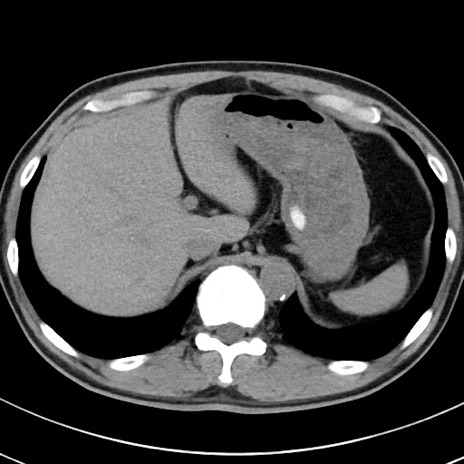

【腹部TIPS】症例29 参考症例 CT(横断像)

症例

70歳代男性